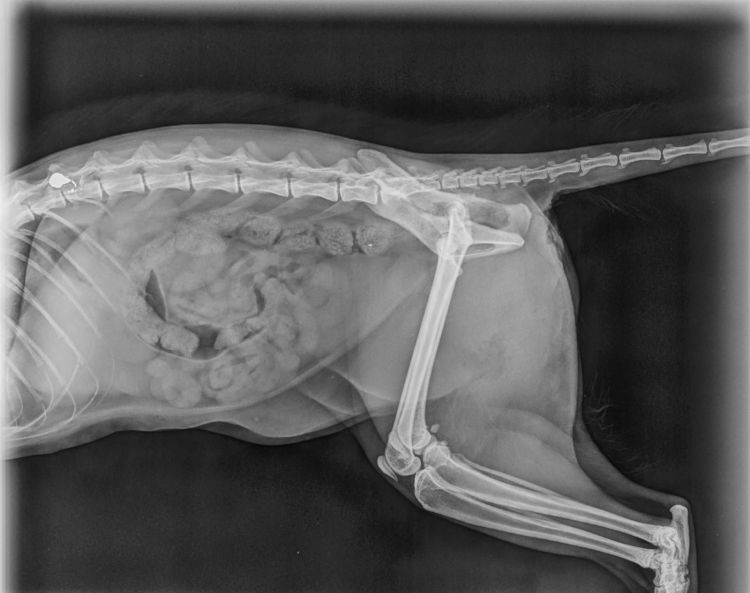

Beschreibung | Man fand Asha regungslos auf der Straße. Sie war unfähig sich zu bewegen und ein beherzter Mann brachte sie zum Tierarzt. Dort wurde sie geröntgt und man stellte fest, dass ein Geschoss in ihrer Wirbelsäule steckte. Es wurde auch noch ein CT gemacht um zu erkennen, ob eine Operation hilfreich wäre. Der Orthopäde befürwortete eine O.P., obwohl er sich nicht sicher war, ob ihr Rückenmark schon zu sehr geschädigt ist, oder ob eine O.P. noch erfolgreich sein könnte. Aber Asha sollte diese Chance bekommen. Es wurde eine Hemilaminektomie durchgeführt, doch während der O.P. stellte man leider fest, dass das Rückenmark zu stark geschädigt war und Asha somit nie wieder wird laufen können. Das war ein großer Schock für alle Beteiligten. Asha ist so eine süße Maus und sie ist sehr traurig, denn leider muss sie derzeit alleine in einer kleinen Box leben. Mit den Vorderbeinchen kann sie sich schon etwas fortbewegen, nur leider sind ihre Vorderbeine zu wenig trainiert, so dass sie sich noch schwer tut. Aber wir wissen es von anderen Fällen, dass sich die Muskulatur prima trainieren lässt und sie sich dann sogar auf das Bett hochkrabbeln oder sich auf den Kratzbaum hochziehen können. Durch ihre Lähmung ist Asha leider inkontinent. D.h. sie hat keine Kontrolle über ihren Schließmuskel und auch nicht über die Blase. Sie hat eine Überlaufblase, die aber dennoch 1x am Tag ausmassiert werden muss. Asha ist so eine liebe Katze. Im ersten Moment ist sie etwas reserviert und zurückhaltend, wenn sie dann aber merkt, dass keine Gefahr besteht, reibt sie ihr Köpfchen an einem und will immerfort gestreichelt werden. Dabei schnurrt sie voller Seligkeit. Sie kann sehr gut mit anderen Katzen zusammenleben. Allerdings darf sie nicht bedrängt werden. Asha könnte sich nicht wehren und das würde sie überfordern. Sie braucht ein ruhiges Zuhause, in dem sie viel Zuneigung und Liebe bekommt. Liebe, schon etwas ruhigere Kinder sind herzlich willkommen. Vor Hunden hat Asha Angst. Es wäre schön, wenn Asha etwas Grün und frische Luft zur Verfügung stehen würden. Eines Tages wird sie ihre Muskulatur an den Vorderbeine gut trainiert haben und kann dann durch die Wohnung flitzen. Da wären auch draußen etwas Rasen und frische Luft super Asha wird FIV und Leukose getestet, Tollwut, Schnupfen, Seuche und Leukose geimpft, entwurmt, gechipt und kastriert abgegeben. |